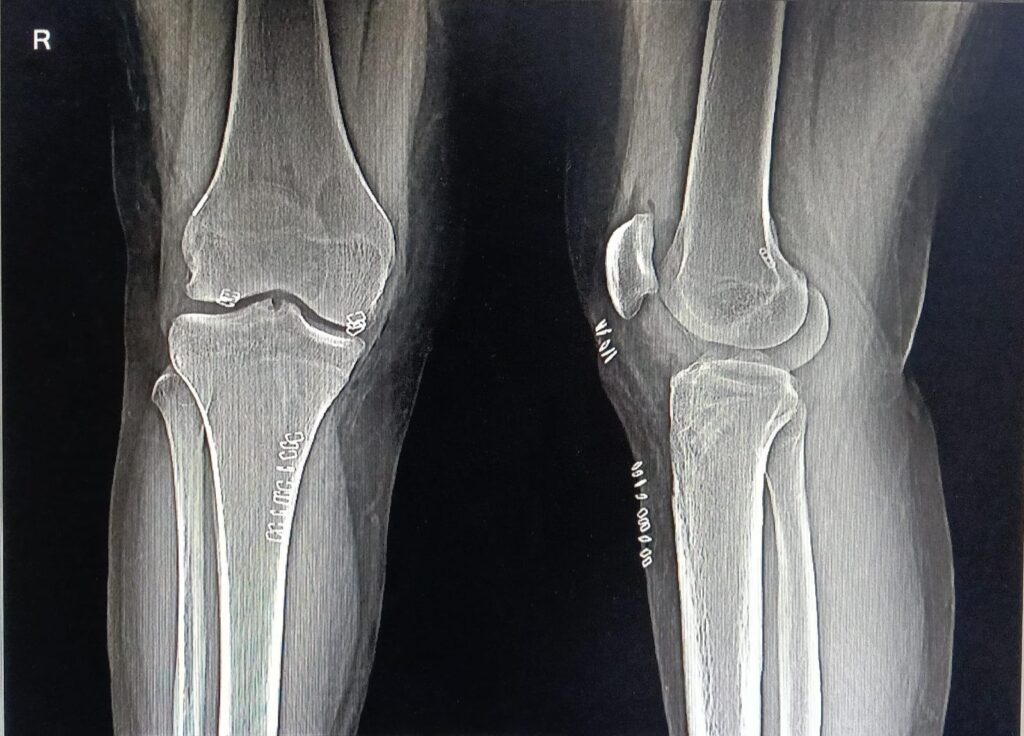

Arthroscopy & Minimally Invasive Procedures

- Joint Knee Arthroscopy (ACL/PCL Reconstruction)

- Meniscus Repair & Meniscectomy

Sports Medicine & Injury Management

- Ligament Injury Treatment (ACL, PCL, MCL)